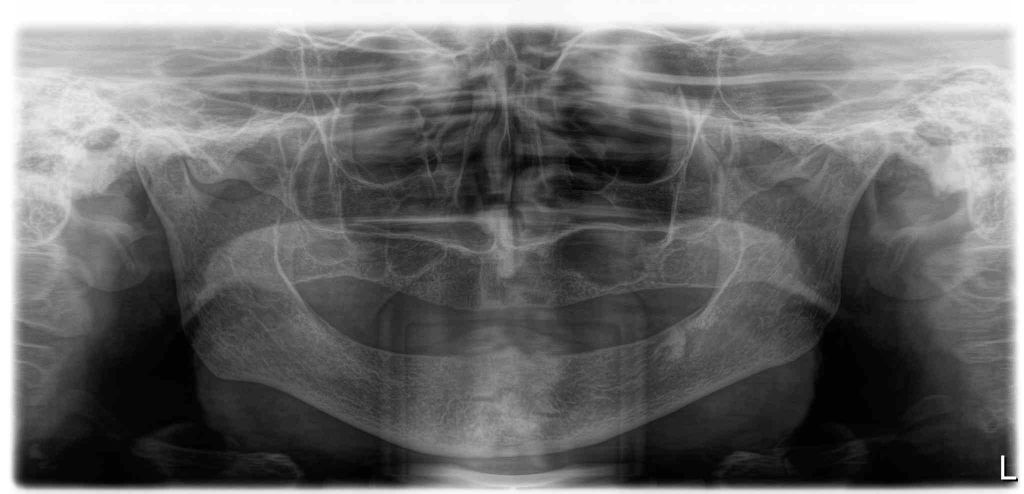

Before